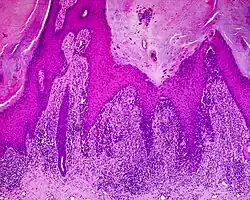

Acral lentiginous melanoma (ALM)

The main characteristic of acral lentiginous melanoma is continuous proliferation of atypical melanocytes at the dermoepidermal junction.[23] Other histological signs of acral lentiginous melanoma include dermal invasion and desmoplasia.[24] This invasion usually occurs many years after the initial lesion first appears.[7]

According to Scolyer et al.,[25] ALM "is usually characterized in its earliest recognisable form as single atypical melanocytes scattered along the junctional epidermal layer".